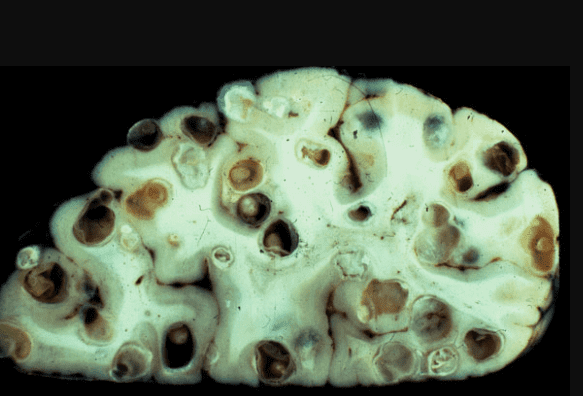

Creierul afectat de paraziți

Un alt caz care m-a șocat cu adevărat. Creierul unui bărbat de 49 de ani era complet populat de paraziți și larvele lor. Cauzele morții - accident vascular cerebral ischemic cerebral. Dar aceasta este doar o consecință! De fapt, paraziții pur și simplu se hrăneau cu țesuturile creierului uman, l-au devorat de viu! În timpul vieții sale, persoana a suferit de dureri de cap, a avut tulburări de somn și memorie. Apoi, când multe zone au fost deja afectate, a fost adăugată epilepsia. Șase luni mai târziu a murit.